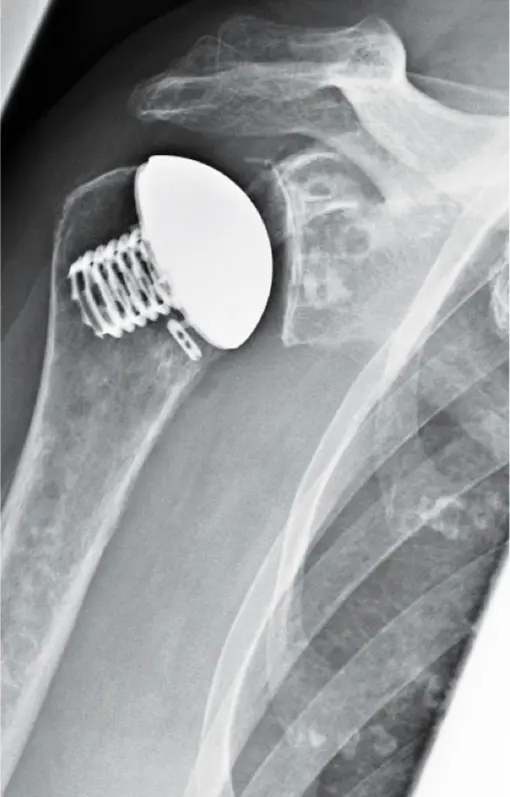

Bei den anatomischen Prothesen unterscheidet man dann weiter auf der humeralen, also der Oberarmseite, zwischen Prothesen mit Schaft (Langschaft- und Kurzschaftprothesen) und der schaftfreien Prothese (Abb. 3) sowie dem Oberflächenersatz. Da die anatomischen Prothesen den Regelfall der Schulter-Endoprothetik darstellen, seien sie hier im Detail beschrieben:

Schaftfreie Prothese

Auch bei diesem Implantat wird der Oberarmkopf entfernt, der Kopfersatz aber ohne Schaft auf der Schnittfläche (Resektionsfläche) befestigt. Vorteil bei den schaftfreien und Kurzschaftprothesen ist, dass sie leichter zu wechseln sind als eine Langschaftprothese, sollte dies nach einigen Jahren notwendig werden (s. u.).